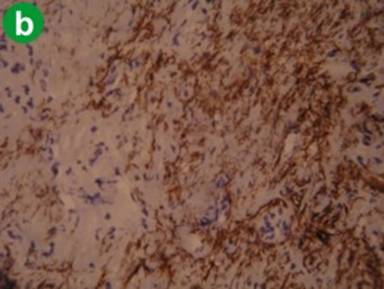

Alcoholic Chronic Pancreatitis

H&E staining showed changes similar to tropical calcific pancreatitis; however, ducts were not as prominent as in cases of tropical calcific pancreatitis (Figure 2a). Staining characteristics on immunohistochemistry with α-SMA and CD34 also were similar to tropical calcific pancreatitis (Figure 2bc).

Figure 2. Representative staining pattern observed in cases alcoholic chronic pancreatitis (a. H&E, b. α-SMA, c. CD34). |